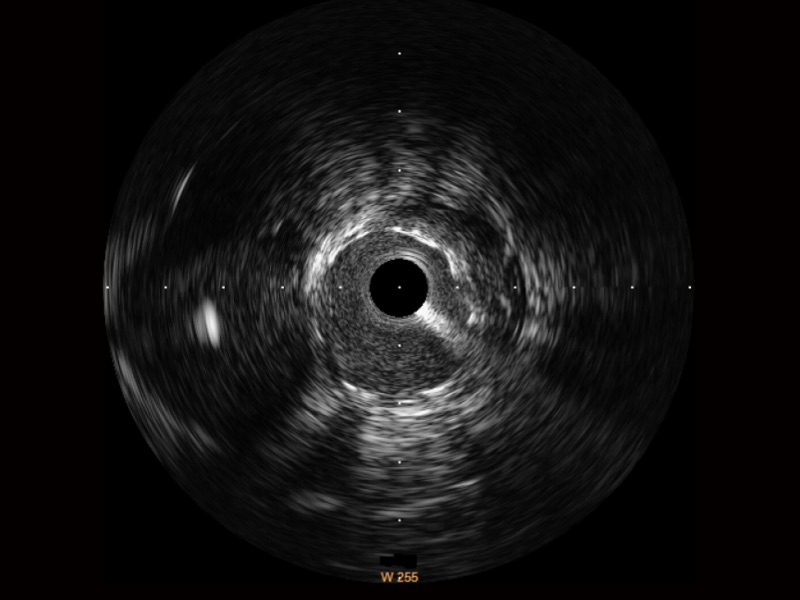

美狮贵宾会官网宽频IVUS图像

对比传统IVUS导管成像,美狮贵宾会官网宽频IVUS图像的近场支架梁显影更细腻,远场中膜外血管仍清晰可辨,兼顾远中近,兼顾分辨力与穿透深度